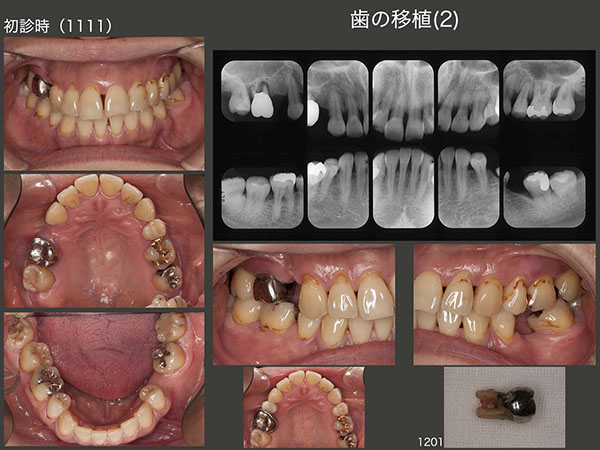

3.歯の移植(2)

2011年11月初診,37歳女性.右上6が腫れたとのこと.この歯は歯周ポケットが5〜8mmあり,動揺も著しく保存不可能と診断した.患者さんは,歯科矯正のために第1小臼歯を4本抜歯しており,なおかつ右上5,左下6も失っていたが,今回さらに右上6が加わった.

上段に右上の経過を示す.まず2012年1月,右上に暫間義歯を装着した.さすがに右上3のクラスプが審美的に好ましくないとのこと.そこで左下8を抜歯し,右上6の欠損部に移植した.(12年2月)

つぎに下段に左下の経過を示す.左下8をドナー歯として抜去したため,前方に傾斜していた左下7のアップライトが可能となった.こうして左下6部のスペースを拡大したのち,今度は右下8を左下6部に移植した.

2014年1月,初診終了時の状態.左下6の移植歯は動揺がみられたため,左下7と連結固定した.同部に,フロスが入らないのが難点である.右上は,犬歯と移植歯との間に半歯分のスペースが残ってしまった.このままスペースを残したままという選択肢もあるが,患者さんは望まなかった.しかし,バージントゥースである右上3を削って,ブリッジにするのは抵抗がある.そこで,神奈川県で開業しているN先生に以前教えていただいた方法を採用した.すなわち,右上6(移植歯)は硬質レジン前装冠の近心にグルーブを細工し,セメント合着した.右上3は歯を一切削去せずに,補綴装置を接着性セメントで付けた.こうしておけば,何時か右上3とポンティックの部分の補綴装置は外れるが,その時また接着すればすむ.すごく良い方法であるが,年がら年中外れてしまっては困る方法でもある.実際,14年11月に1回外れたが,その後は何とか外れないでいる.